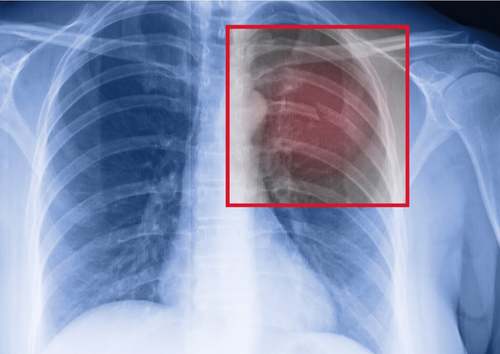

Se siete degli sportivi e soffrite di una frattura costale da stress, prima di tutto dovete consultare un medico. Vi faranno una radiografia del torace per confermare la lesione e valutarne l’estensione.